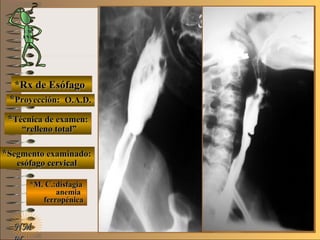

*Rx de Esófago*Rx de Esófago

**Proyección:Proyección:

**Técnica de examen:Técnica de examen:

**Segmento examinado:Segmento examinado:

*M. C.:disfagia*M. C.:disfagia

anemiaanemia

ferropénicaferropénica

NMNM

O.A.D.O.A.D.

““relleno total”relleno total”

esófago cervicalesófago cervical

A-A-El examen es normal o patológico?El examen es normal o patológico?

Examen patológico de esófago cervical, conExamen patológico de esófago cervical, con

relleno total en proyección O.A.D.relleno total en proyección O.A.D.

B-B-La patología es congénita o adquirida?La patología es congénita o adquirida?

Patología congénitaPatología congénita

C-C-Puede describir la o las imágenes patológicas?Puede describir la o las imágenes patológicas?

**OpciónOpción

de volverde volver

a ver lasa ver las

imágenesimágenes

Se identifica una pequeña “indentación” enSe identifica una pequeña “indentación” en

el borde antero-superior del esófago cervicalel borde antero-superior del esófago cervical

inmediatamente por debajo de la unión faringoinmediatamente por debajo de la unión faringo

esofágica o “boca de Killian” a nivel de C6, queesofágica o “boca de Killian” a nivel de C6, que

disminuye el calibre esofágico afectando el flujodisminuye el calibre esofágico afectando el flujo

laminar del contraste y provocando el efecto delaminar del contraste y provocando el efecto de

““chorro de jet” con alteración de la homogenei-chorro de jet” con alteración de la homogenei-

dad de la columna baritada (Síndrome de Plu-dad de la columna baritada (Síndrome de Plu-

mmer-Vinson)mmer-Vinson)

**Opción avanzada para volver a ver las imágenes con reparosOpción avanzada para volver a ver las imágenes con reparos

**Proyección: O.A.D.Proyección: O.A.D.

tabique otabique o

membranamembrana

efecto deefecto de

““chorrochorro

de jet”de jet”

volvervolver